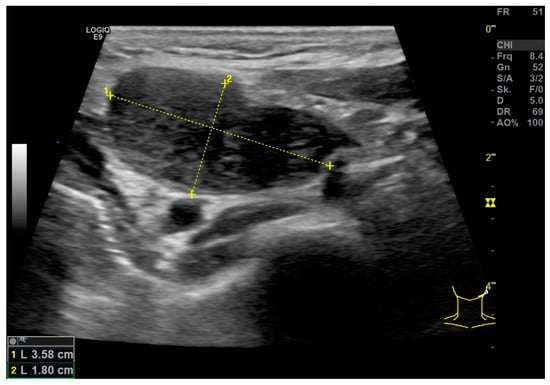

| B-Scan | Identification of clinically suspected LN metastases | - |

| CCDI incl. B-Flow | Vascularization pattern | - |

| Strain Elastography | Qualitative report of stiffness (soft or hard) | Q-analysis of strain elastography with Q-ratio; two ROI in the center, four at the margin of the LN and two in the surrounding soft tissue. The ROIs within the LN included areas with the lowest and the highest stiffness. The diameter of each ROI was 2–3 mm. |

| Shear Wave Elastography | Single ROI drawn with the largest possible diameter not extending beyond the LN margins (kPa). | Repeated (3x) measurement by kPa and m/s using ROI drawn with the largest possible diameter not extending beyond the LN margins. The values of the repeated measures were used to build a mean value for overall LN stiffness in kPa and m/s. |

| CEUS | Perfusion and enhancement dynamics (Wash-in/Wash-out) | Time–Intensity Curve analysis with Time-to-Peak and Area-under-the-Curve; two ROI in the center, four at the margin of the LN and two in the surrounding soft tissue (outside of vessels). For the correct placement of ROI, only positive values were accepted (adjustment for artefacts). The diameter of each ROI was 2–3 mm. Additionally parametric evaluation of the perfusion kinetics. |